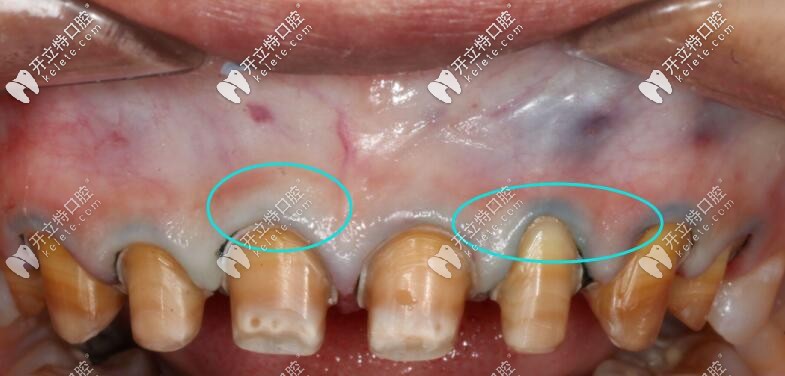

使用Procera全瓷牙修復(fù)不會(huì)出現(xiàn)以下這種情況喲↓↓↓

使用Procera全瓷牙修復(fù)不會(huì)出現(xiàn)以下這種情況